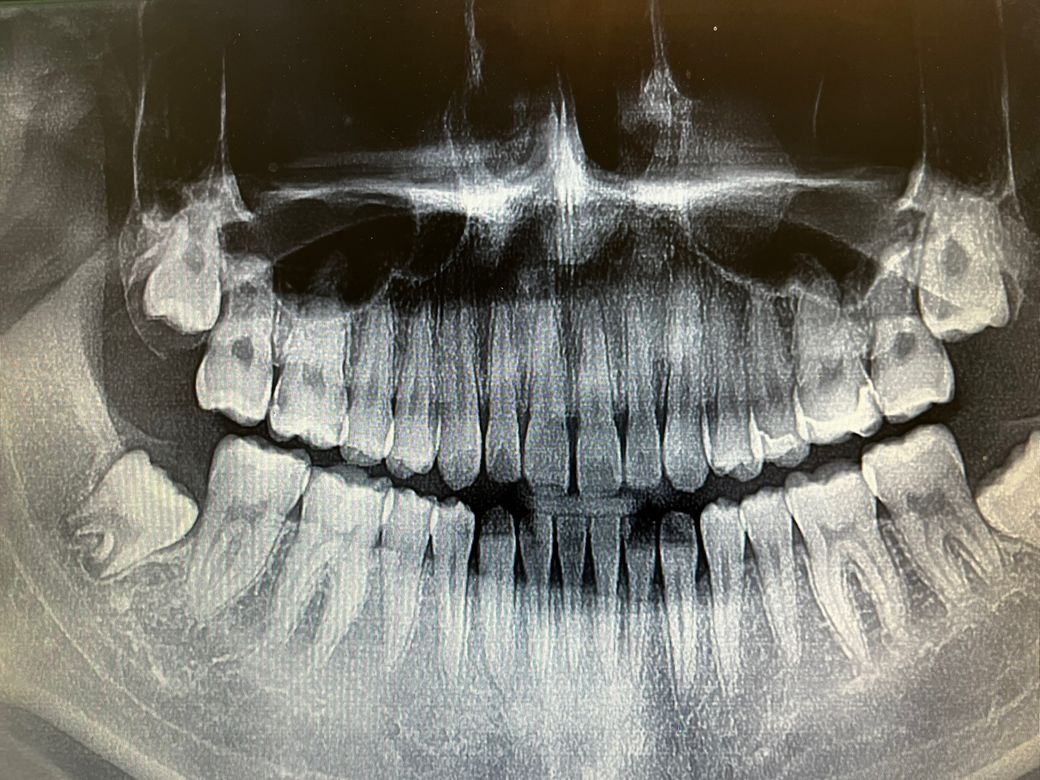

작년 치아 사진입니다 제 사랑니는 매복인가요? 만약 뽑아야한다면 소요시간이 얼마나 걸릴까요? 많이 아픈가요? 4개 다뽑아야할까요

• 1번 째 사진

1. 20대 초반까지는 아직 맹출력이 있고, 앞 어금니와의 각도를 고려해보면 좀 더 맹출할 것 같습니다

2. 보통 한쪽씩 왼쪽, 오른쪽 위+아래 뺍니다. 각각 30분 정도 잡으시면 됩니다.

3. 당장 뺄 필요는 없어보입니다.